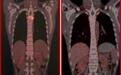

图1. 首次CD7 CAR-T细胞治疗及桥接移植后胸椎肿块完全缓解